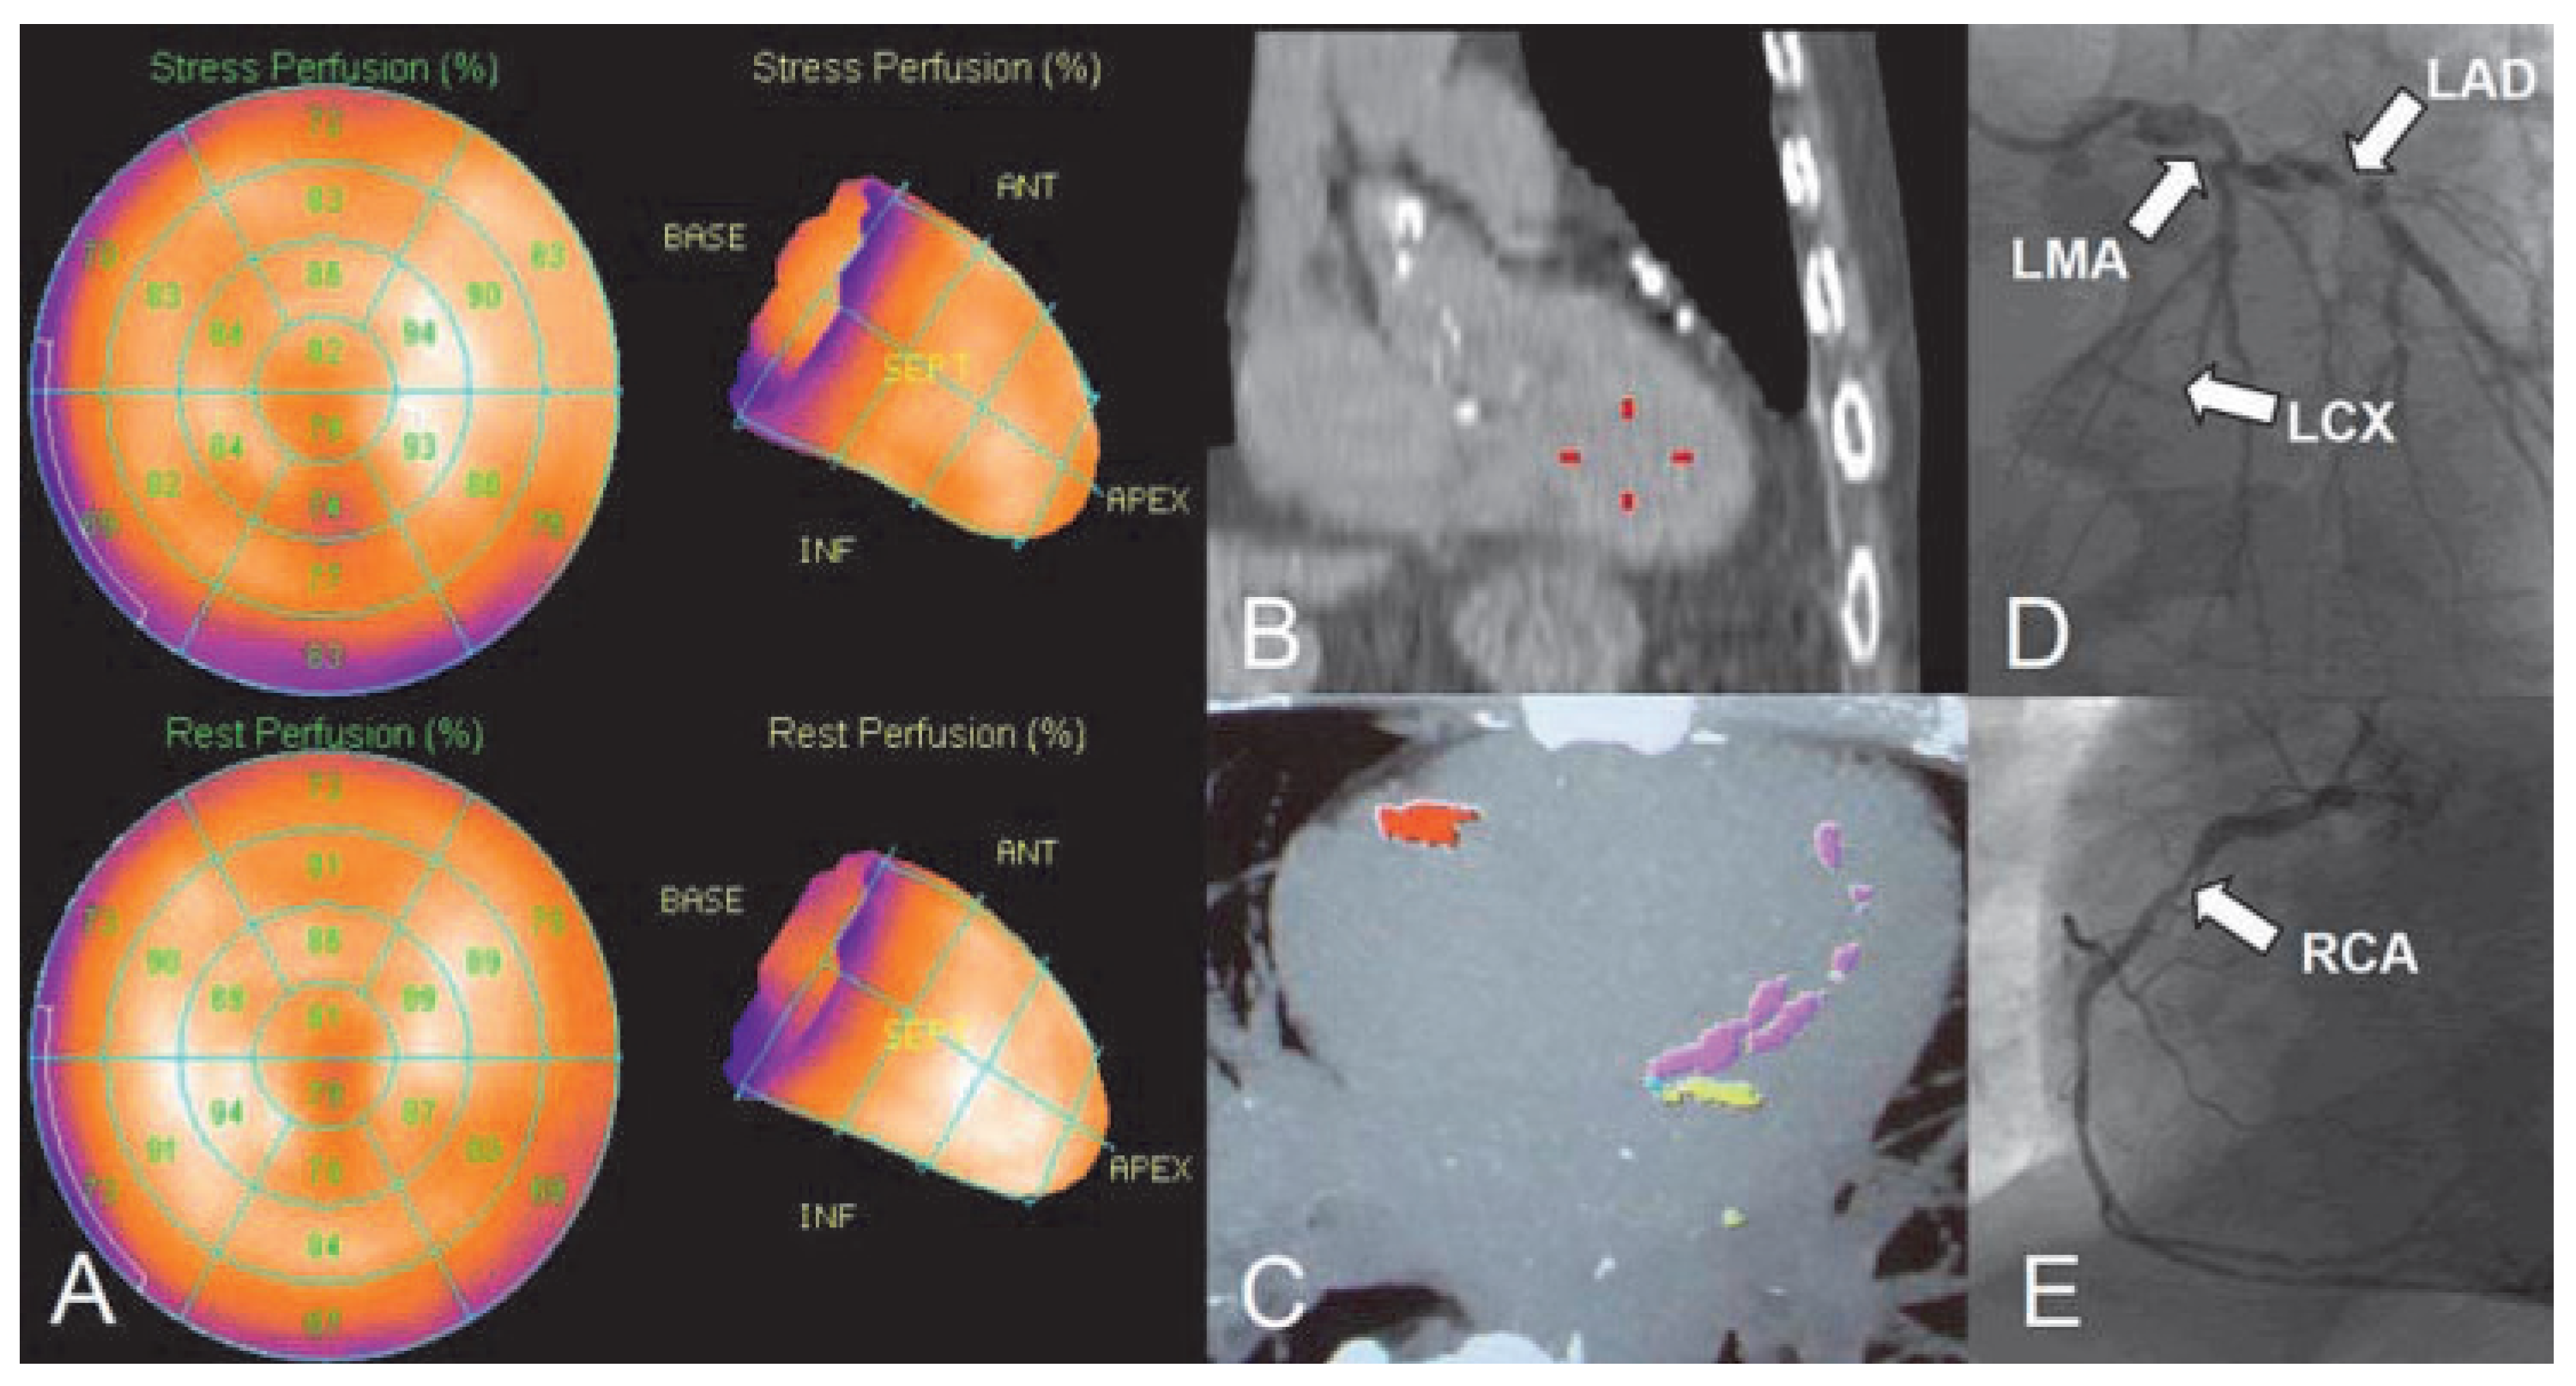

![]() |